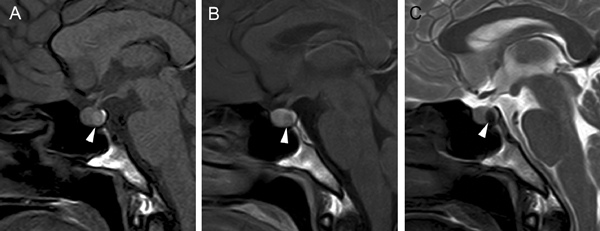

En los tumores grandes (macroadenomas) la TAC puede entregar información diagnóstica adecuada, pero no supera la definición que se logra con equipos de RM superconductores (Figuras 2 A y 2B).

Figura 2A y B. Cortes sagitales de RM y TAC. Adenoma pituitario con invasión del esfenoides y del clivus (puntas de flecha). Es posible demostrar las estructuras óseas en RM con similar precisión que la TAC.

Figura 12A. Microadenoma pituitario (8 mm), corte coronal, secuencia convencional T1w con Gadolinio, el tumor lateralizado a derecha, erosiona y deforma el piso de la silla turca (punta de flecha). B. Mismo paciente, 3 meses post-tratamiento médico, corte coronal secuencia T1w con Gadolinio, El tumor ha modificado su forma, se ha reducido de tamaño (punta de flecha) y la glándula muestra ahora un borde superior cóncavo, con una pequeña herniación de la cisterna supraselar. Los macroadenomas pituitarios producen expansión de la silla turca, con moderado refuerzo del tumor después de la inyección de gadolinio. La densidad (TAC), intensidad de señal (RM) y características del refuerzo con medio de contraste yodado (TAC) o gadolinio (RM) no son específicas, pero el aumento de volumen y erosión de la silla turca, la invasión del seno cavernoso y la presencia de contornos lobulados (64%) son hallazgos frecuentes en un macroadenoma42-44. El aumento de volumen selar se observa en 94 a 100% y la erosión de las paredes de la silla turca, incluyendo el piso selar, dorso selar, tubérculo selar y extensión al seno esfenoidal, está presente en 76% de los macroadenomas. La invasión del hueso esfenoides y del clivus (Figura 2Ay 2B) se demuestra en 19% de los casos.